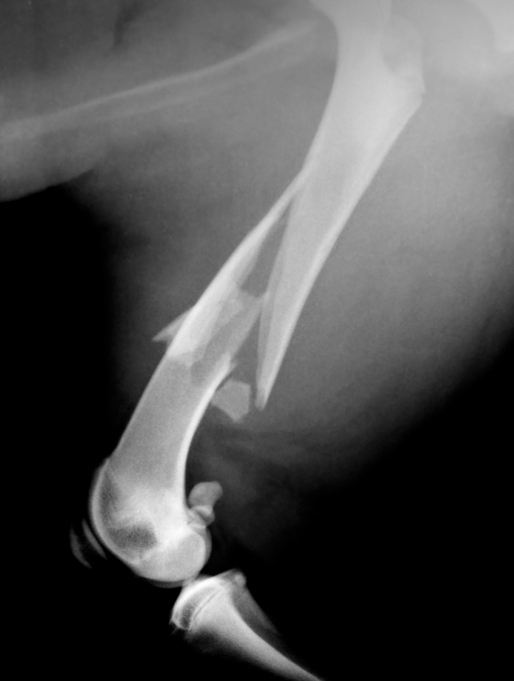

Перелом бедра у собаки

Перелом бедра у собаки 113 фотографий